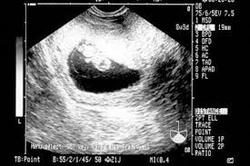

آنلاین؛ صدای قلب نوزادتان را بشنوید محققان موفق به اختراع دستگاه سونوگرافی شده اند که به‌صورت آنلاین، صدای قلب نوزاد را دریافت می‌کند.

سرویس جامعه جوان آنلاین: در گذشته که دستگاه‌های سونوگرافی اختراع نشده بودند حتی خانواده‌ها نمی‌دانستند که فرزندشان دختر است یا پسر، اما رفته رفته با توسعه تکنولوژی و به‌وجود آمدن دستگاه‌های سونوگرافی، آن‌ها توانستند از سلامت فرزند خود باخبر شوند.

به تازگی دانشمندان موفق به اختراع دستگاه سونوگرافی آنلاین شده اند. این دستگاه سونوگرافی آنلاین به صورت مجازی و در هر دقیقه زمانی صدای قلب بچه را دریافت می‌کند و به کمک برنامه‌های تخصصی پزشکی که درون گوشی نصب می‌شوند به تحلیل صدای قلب کودک می‌پردازد.

از جالبترین خصوصیات و ویژگی‌های این دستگاه سونوگرافی آنلاین می‌توان به پردازش و ارسال صدای قلب کودک به دیگر اعضای خانواده اشاره کرد به طوری که شما می‌توانید صدای قلب کودک تان را ذخیره کنید و آن را به صورت آنلاین و مجازی برای پدر فرزندتان بفرستید.